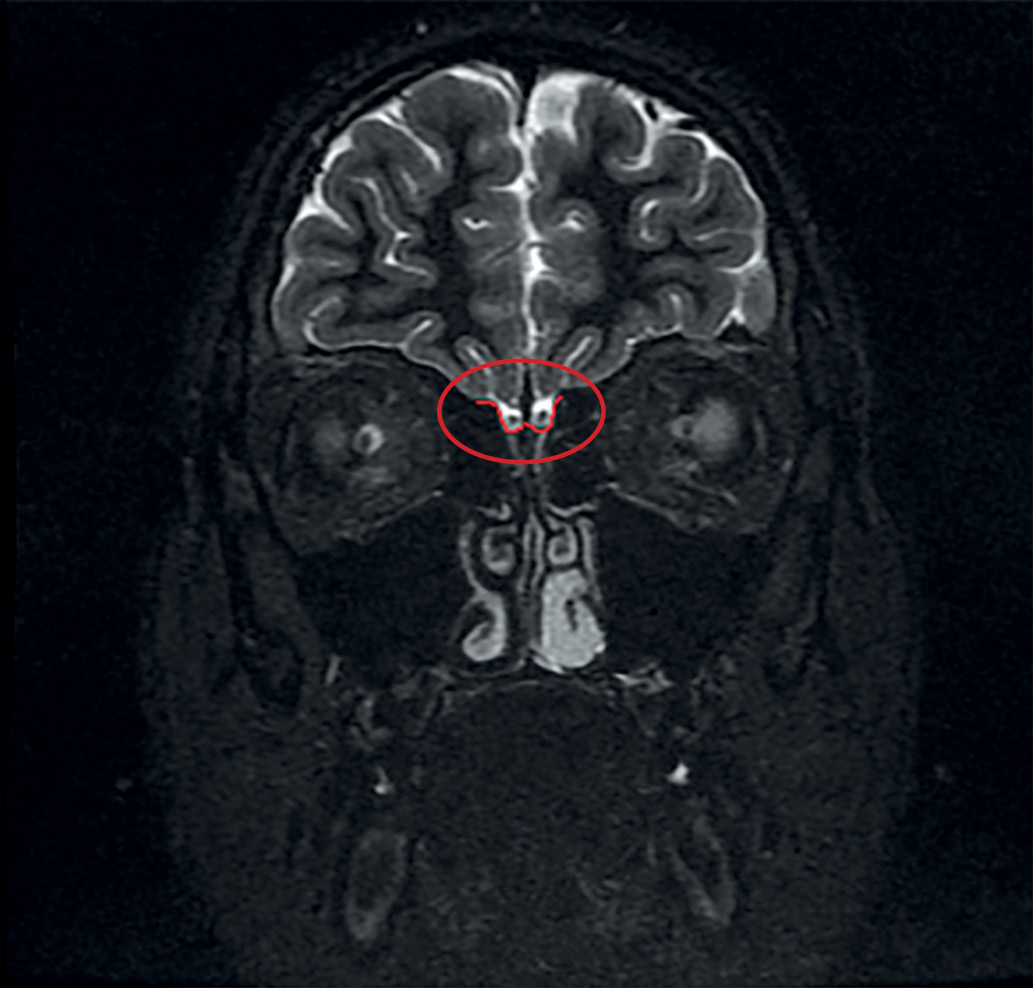

По результатам МРТ у 18 из 19 пациентов с ВИГГ наблюдалось снижение размеров ОЛ или их полное отсутствие. Практически у каждого третьего пациента отмечалась гипоплазия обеих луковиц (7 пациентов). Реже отмечалась односторонняя гипоплазия (27,8%), двусторонняя аплазия (16,6%), гипоплазия одной луковицы в сочетании с аплазией другой (11,1%). Аплазия одной луковицы имелась у 1 пациента. На рисунках 1 и 2 выделена область обонятельных луковиц нормального размера у пациентки из контрольной группы и область с аплазированными ОЛ у пациента с синдромом Кальмана.

Рисунок 2. Аплазия обонятельных луковиц у пациента с синдромом Кальмана.